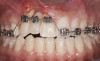

Fig 8. Compared to the preoperative view seen in Fig 2, adequate alveolar height and gingival profile were achieved with forced eruption (Fig 8). Direct composite splint would remain for 3 months. Residual cleft was a visible remnant of iatrogenic defect. Post-orthodontically, keratinization of sulcular epithelium on tooth No. 8 was evident (Fig 9).

Figure 8

Fig 9. Compared to the preoperative view seen in Fig 2, adequate alveolar height and gingival profile were achieved with forced eruption (Fig 8). Direct composite splint would remain for 3 months. Residual cleft was a visible remnant of iatrogenic defect. Post-orthodontically, keratinization of sulcular epithelium on tooth No. 8 was evident (Fig 9).

Figure 9

When forced eruption is completed, the teeth should be splinted for a 3-month stabilization period,30 which will allow mineralization of osteoid tissue and settling of the gingival remodeling process. The degree of forced eruption in the present case was such that extreme mobility precluded the use of a provisional restoration. Instead, a metal-reinforced direct composite splint extending from teeth Nos. 6 to 8 was fabricated in situ (Figure 8 and Figure 9). When compared with the preoperative condition (Figure 2), Figure 8 and Figure 9 depict the treatment progression with forced eruption. The restoration of adequate alveolar height was achieved while enhancing the soft-tissue architecture, and the everted sulcular epithelium on tooth No. 8 proceeded to develop keratinization. However, the pre-existing defect still manifested itself in the form of a residual cleft.